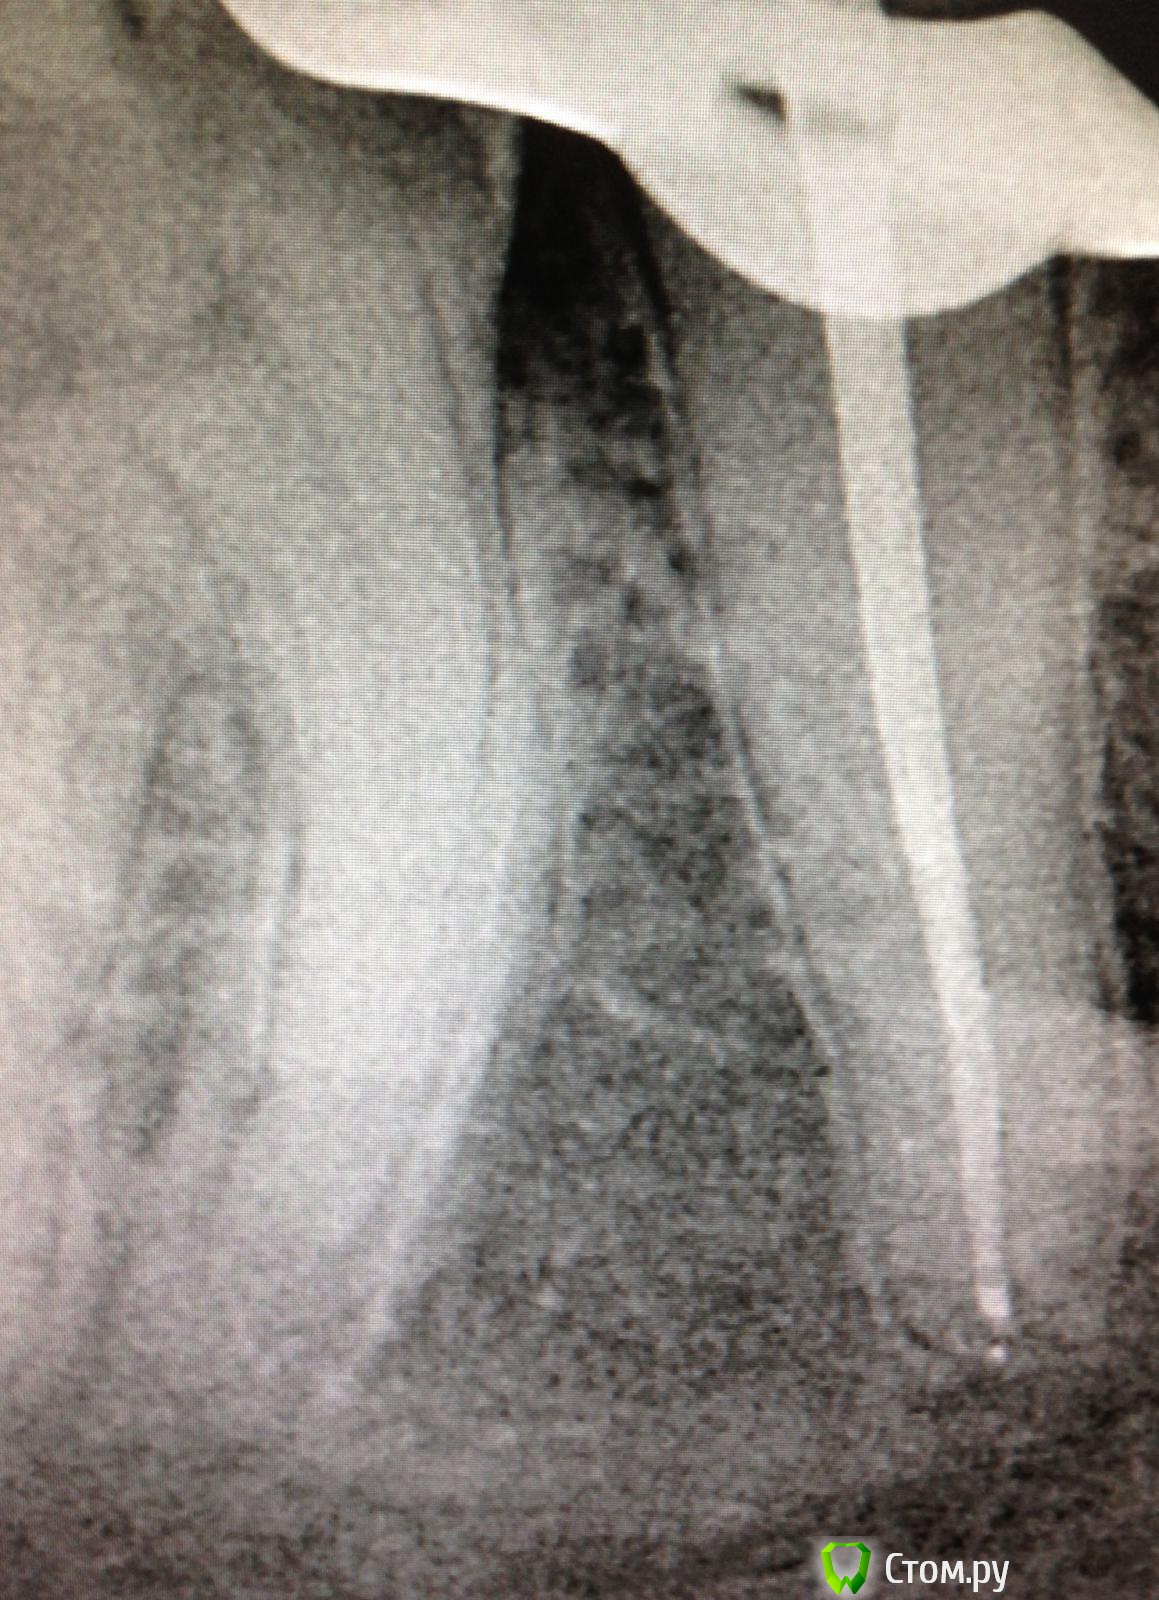

SSTi Опубликовано 28 июня, 2014 Автор Поделиться Опубликовано 28 июня, 2014 37 выпала пломба- вскрытая точка - пульпит. 2 вопроса. 1- как вы предотвращаете выход силера за верхушку при изначально широком апикальном отверстии?( как здесь в дистальном)2. - нет подозрений по снимку на 3й канал медиальный??мед устья были смещены сильно щечно. Расстояние между ними 1-1.5 мм. Были скрыты под дентиклем. Меня посещают мысли, что это мщ и мм. А не мщ и мя. Хотя от устья дистального сулькус шел и раздваивался только в направлении этих двух. Второй снимок - под углом. Датчик медиально, трубка дистально. Ссылка на комментарий

faity Опубликовано 29 июня, 2014 Поделиться Опубликовано 29 июня, 2014 да и Будда с силлером, пусть выходит в разумных пределах)канала вроде нет, для очистки совести сделай КТ, Сереж. Ссылка на комментарий